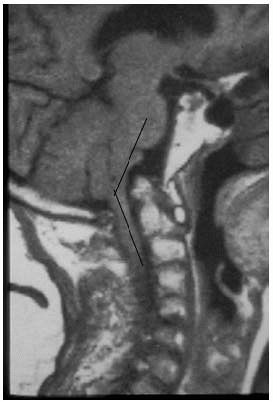

![]() |

FIGURE 11-9.

Lateral plain radiographs and sagittal T2 MRI in a patient with multilevel congenital cervical stenosis with associated spondylosis causing severe cord compression, including signal change within the cord, in a patient with spastic gait and clumsy hand consistent with cervical myelopathy (A, B). Because of the multilevel nature of the problems the treatment selected was a posterior laminoplasty with excellent recovery of neurological complaints (C, D). |

FIGURE 11-9. (Continued)